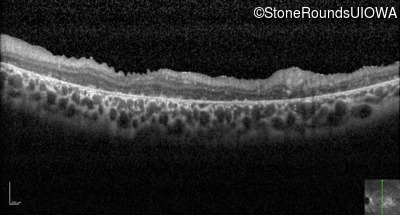

Optical Coherence Tomography - Left - 20/400 sc

Exemplar / OCT Stack